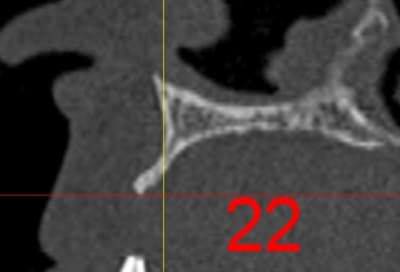

La première diapo est un essai pour justifier le concept (os non destiné à une utilisation greffe)

la deuxième est "tapée" dans une tête de femur de mauvais qualité (rejetée)

la troisième et suivante ce sont "les greffons" définitifs.

La précision 3D du scan est elle suffisante pour une adaptation passive sur l'os réel ?

La tu nous montres sur un stereolitique obtenu à partir du scan, ok ça colle mais en bouche ?